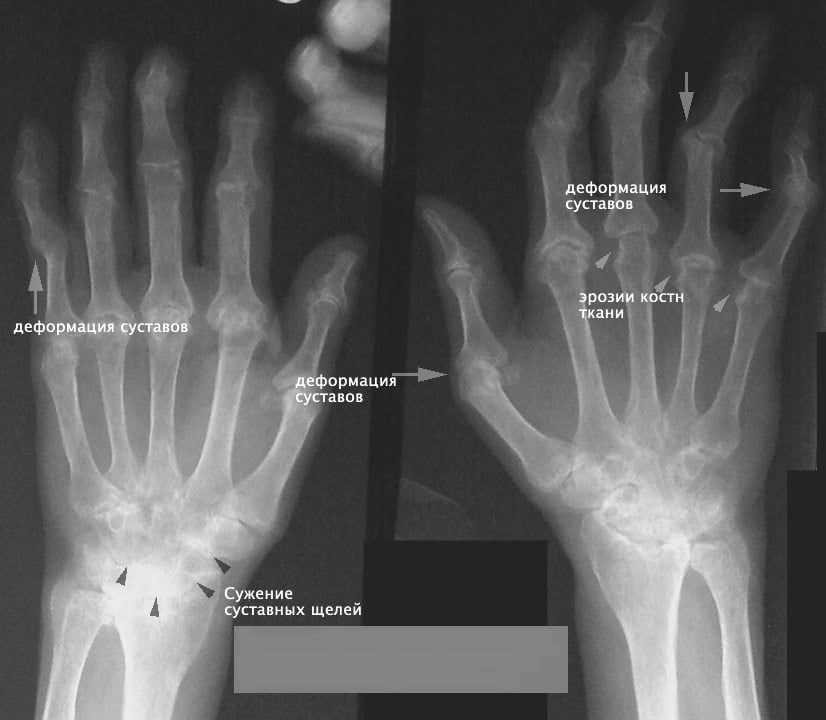

Клиническая картина артрита пальцев рук отличается большой вариабельностью и зависит от этиологической формы и стадии болезни. Ранней стадии ревматоидного артрита свойственна скованность суставов по утрам и после длительного покоя. При этом возникает характерное ощущение тугих перчаток, ограничивающих подвижность кисти. В отдельных случаях у пациента может вовсе не быть жалоб, а единственными проявлениями заболевания служат ранние рентгенологические признаки артрита пальцев рук:

- утолщение и уплотнение мягких тканей;

- незначительное сужение отдельных межсуставных щелей;

- околосуставный остеопороз;

- единичные кистовидные просветления в костной ткани;

- шероховатости и эрозии на суставных головках костей.

Характерные признаки воспаления суставов пальцев, как правило, наблюдаются на II стадии заболевания, начиная с появления болезненной припухлости, эритемы и крепитации в пораженных суставах, а к рентгенологическим признакам прибавляются множественные сужения межсуставных щелей, кистовидные просветления костной ткани и краевые деформации эпифизов костей. Вывихи, подвывихи и анкилозы суставов выявляют преимущественно на терминальных стадиях заболевания.

- характерных данных рентгенологических исследований, способных обнаружить такие патологические изменения как: утончение суставной щели, присутствующие анкилозы, эпифизарный остеопороз, узурацию костных поверхностей пораженных суставов и т.д.;

Сама по себе рентгенологическая картина артритов достаточно многообразна и может включать такие визуальные признаки:

- практически все разновидности остеопороза;

- частичное или тотальное утончение суставной щели или в некоторых случаях ее расширение, связанное с деструктивными повреждениями костно-хрящевых тканей сустава;

- наличие костных узур (краевых дефектов по типу эрозий) на соответствующих поверхностях проблемных суставов как следствие проходящих в них дегенеративных процессов;

- существование очагов активной деструкции в околосуставной костной области;

- образование секвестров (тканевое омертвение), наблюдаемых зачастую при специфических видах артритов (например, при туберкулезном);

- формирование периостальных наслоений в районе костных метафизов, а также возникновение реактивного остеосклероза;

- трансформация рельефа костных поверхностей патологических суставов и краевые разрастания на них;

- подвывихи и вывихи, образующиеся в ответ на суставную деформацию (типичны для некоторых артритов, включая ревматоидный).